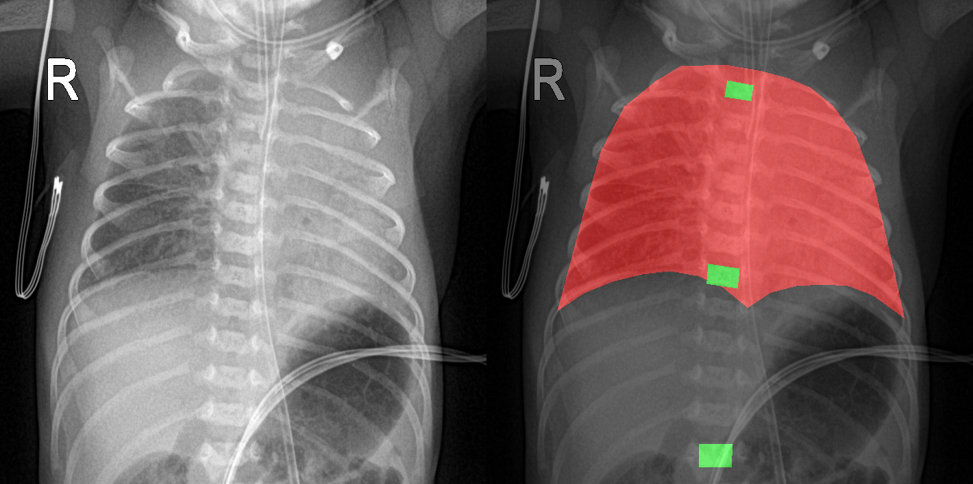

27일 코어라인소프트는 신생아 흉부 X-ray 영상에서 주요 기준점인 흉추 T1, T7, T12를 자동 분할해 표시하는 시스템을 개발했다고 밝혔다.

코어라인소프트의 딥러닝 기반 모델을 활용해 분석한 결과 세 흉추 위치 모두에서 90% 이상의 식별 정확도를 보이며 기술적 안정성을 입증했다는 설명이다.

이번 연구는 카테터나 기관삽관 튜브의 위치를 직접 판단하는 기존 방식과 달리, 위치 평가의 기초가 되는 해부학적 영역을 정의하는 데 초점을 맞췄다.

신생아의 체격 차이나 다양한 촬영 환경에도 불구하고 해부학적 구조를 안정적으로 포착해냄으로써 판독의 객관적 표준을 제시할 수 있는 토대를 마련했다는 평가다.